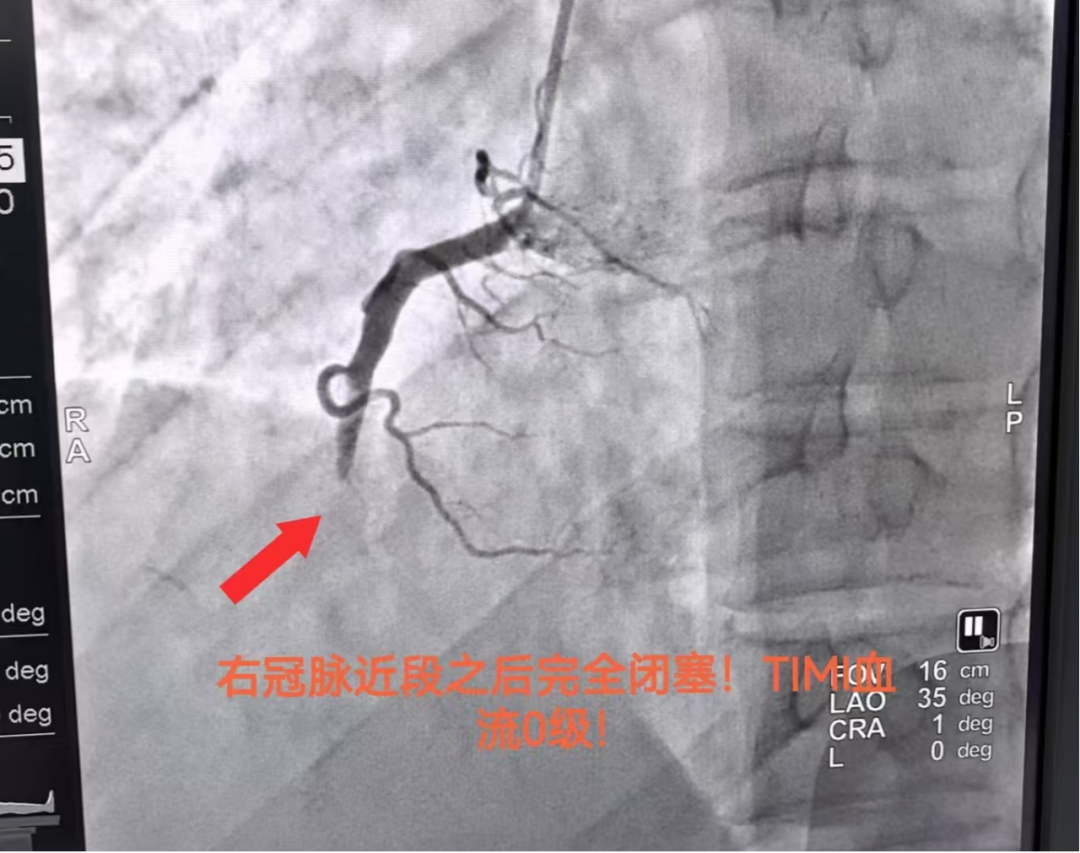

该患者入院前 1 小时因饮酒后突发胸前区剧烈疼痛、大汗淋漓,伴濒死感!胸痛持续无法缓解,我院心电图提示Ⅱ、Ⅲ、aVF 导联 ST 段明显抬高!典型的急性下壁心肌梗死,病情极凶险、随时可能危及生命,经我院 DSA 心内介入团队全力救治后成功开通梗死血管,将患者从「死神」手里抢回。